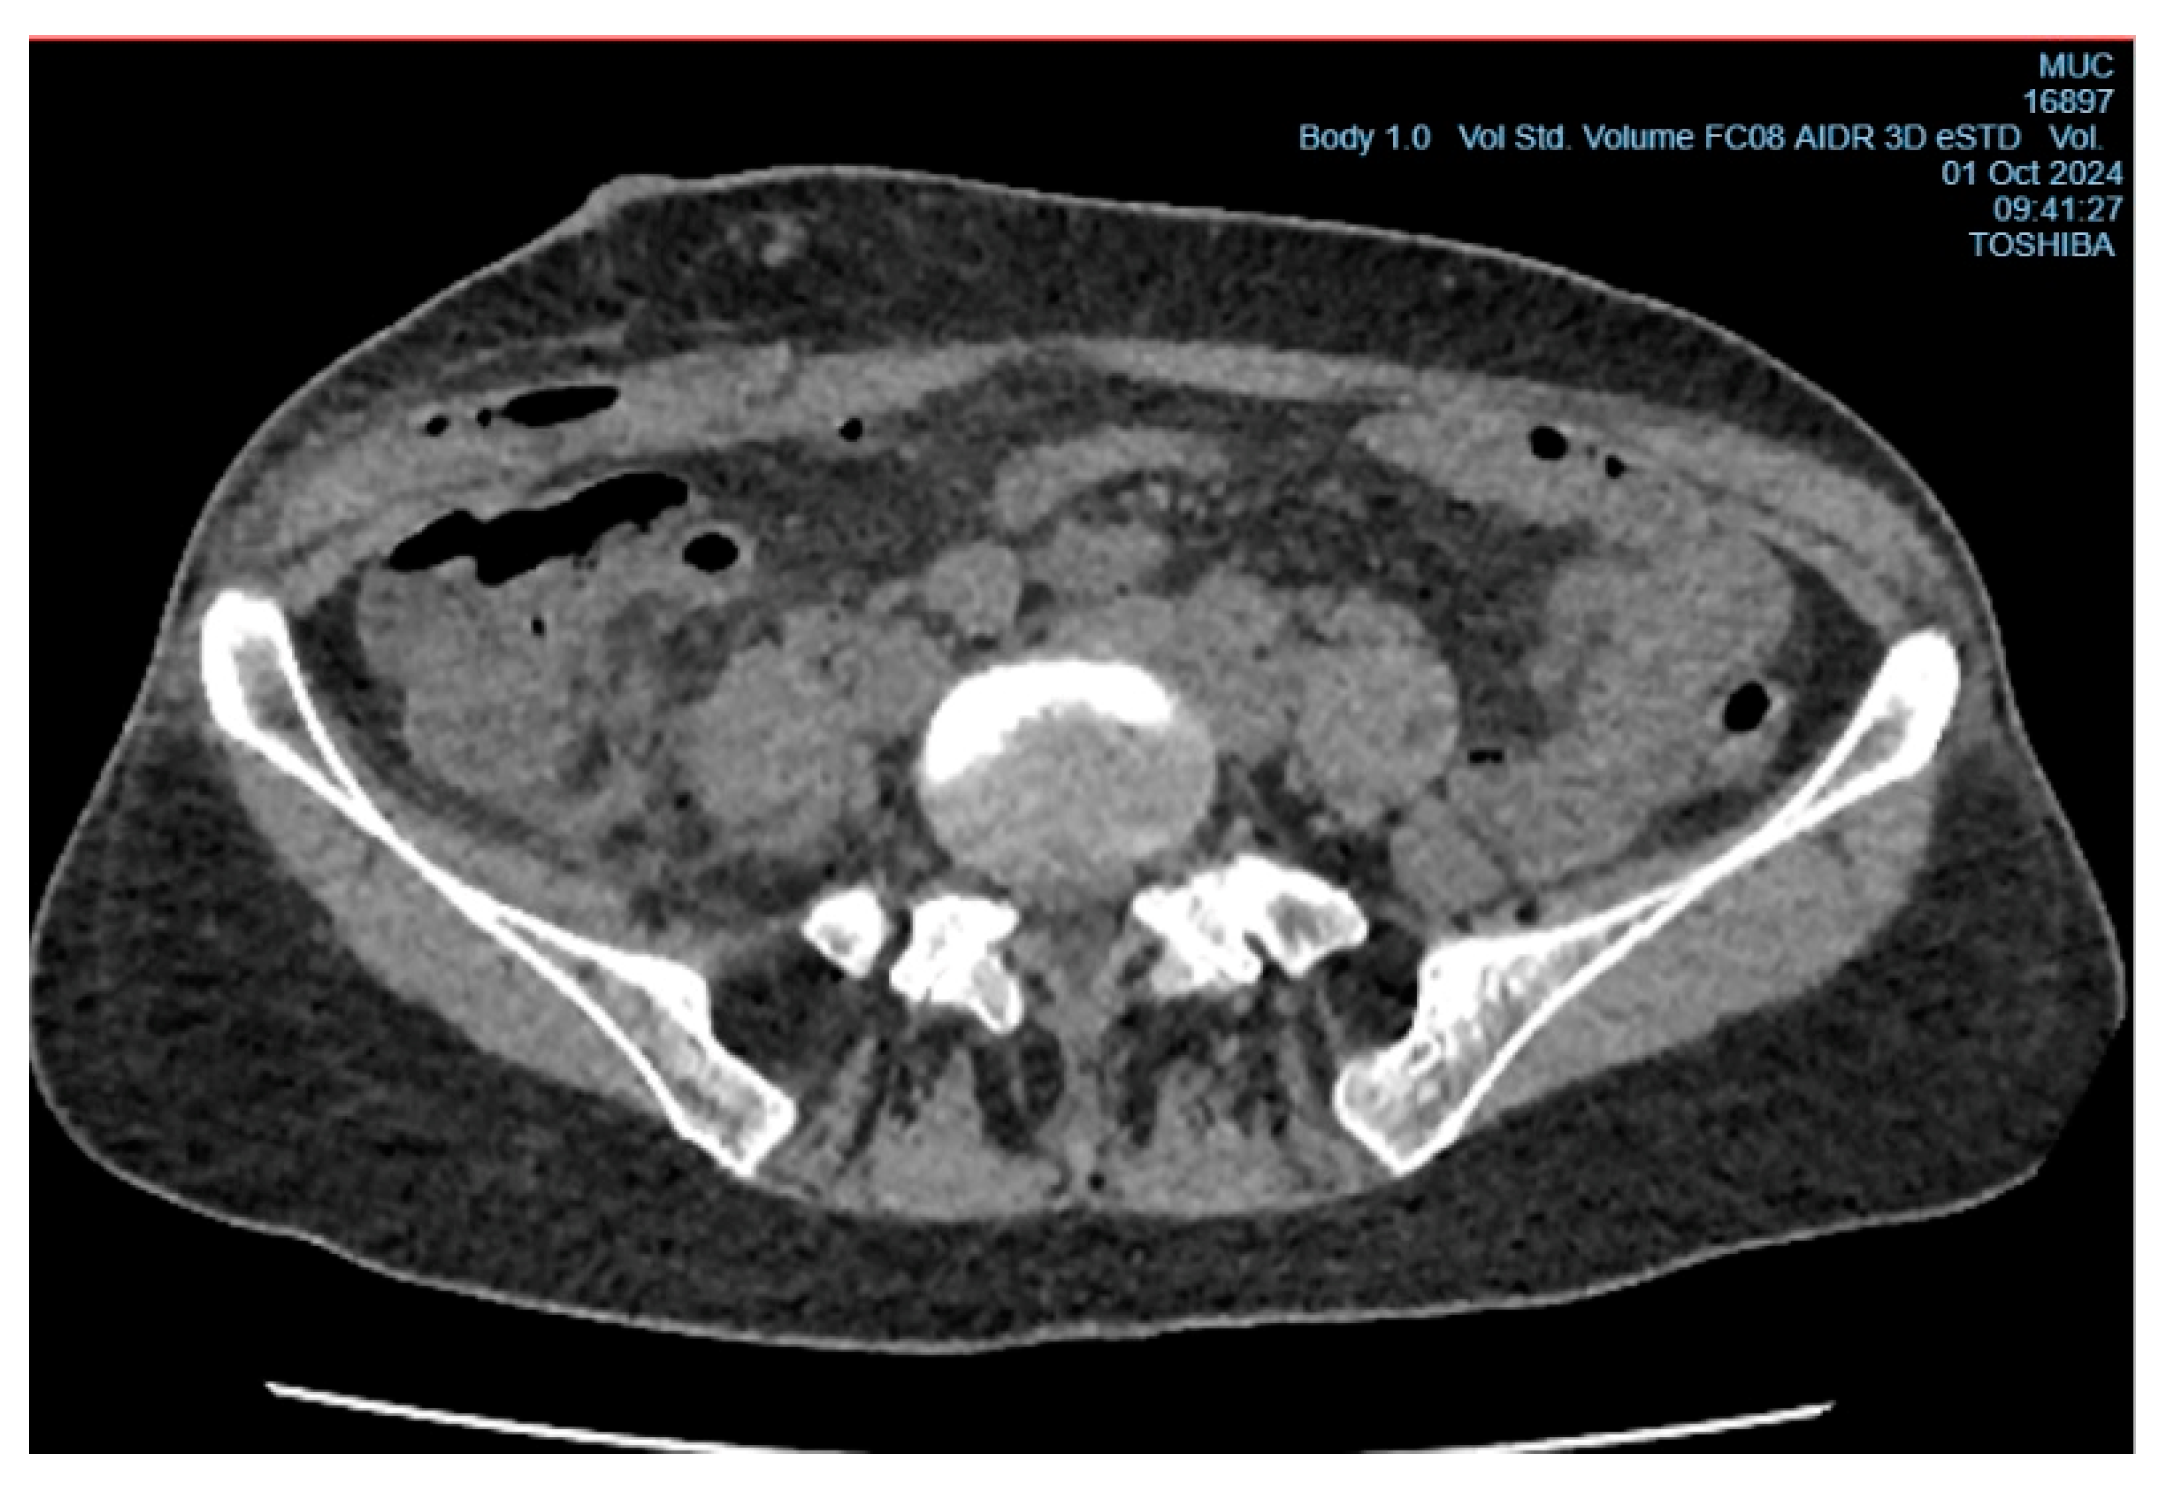

In the early postoperative period, the patient had a persistent elevated body temperature of 37.5°C–38.0°C, localized tenderness at the site of the surgical wound, but no local hyperemia. Leukocytosis was observed (11.2×10⁹/L, reference range from 4 to 9×10⁹/L) with an increase in neutrophils (neutrophils - 78%, reference range from 35% to 70%, band neutrophils - 4%, reference range from 1% to 5%). Despite antibacterial therapy (Cef III, 1.0 gram intramuscularly twice daily), no clinical improvement was observed, raising suspicion of a subgaleal abscess of the postoperative wound (Figure 3). On the 6th day after surgery, the patient underwent wound revision under local anesthesia with 0.5% Novocain solution (30 ml). During the procedure, a collection of pus under the aponeurosis of the external oblique abdominal muscle was diagnosed, and the abscess cavity was drained (Figure 4). A sample for microbiological analysis was collected and sent to the research laboratory of the Karaganda Medical University.

Figure 3. CT image of a subgaleal abscess in the area of the postoperative wound in the right iliac region.